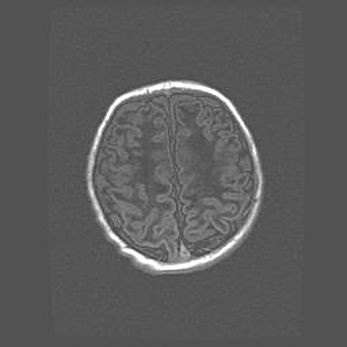

Ниже представлена  галерея МРТ снимков, полученных с применением LMT неонатальных матричных РЧ катушек. Также каждая группа МРТ снимков сопровождается информацией о пациенте (диагноз, возраст, вес, пол, срок гестации) и краткой сопроводительной расшифровкой диагноза.

Церебральная ишемия II.

Возраст: 7 дней

Вес: 3350 г

Пол: женский

Окружность головы: 35 см

Срок гестации: 39 недель

Ишемия головного мозга – это состояние, которое развивается в ответ на кислородное голодание вследствие недостаточного мозгового кровообращения. У новорожденных она является следствием дефицита кислорода, что ведет к метаболическим расстройствам различной степени тяжести в тканях головного мозга, в том числе к развитию коагуляционных некрозов и гибели нейронов.